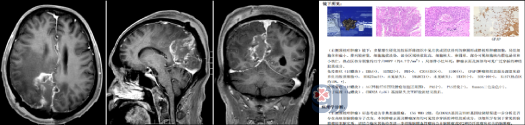

术后,冯先生恢复顺利,复查头颅MR显示病变已完全切除。出院时,他神志清醒,左侧肢体无力症状显著改善,四肢活动自如,家属悬着的心也终于落地。术后病理结果明确为:非典型脑膜瘤,CNS WHO 2级。

2级(非典型): 如本例患者,属于交界性肿瘤,具有一定的复发倾向,对手术全切要求更高,术后需长期密切随访。